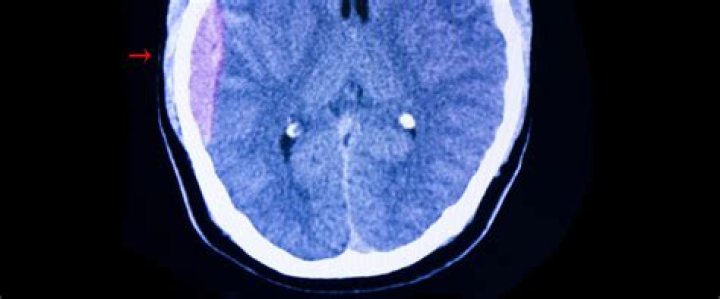

Complications. A severe head injury can result in pressure being placed on the brain because of bleeding, blood clots or a build-up of fluid. This can sometimes lead to brain damage, which can be temporary or permanent.

• Intracranial hematoma (ICH). This is bleeding under the skull in the brain that forms a clot. ...